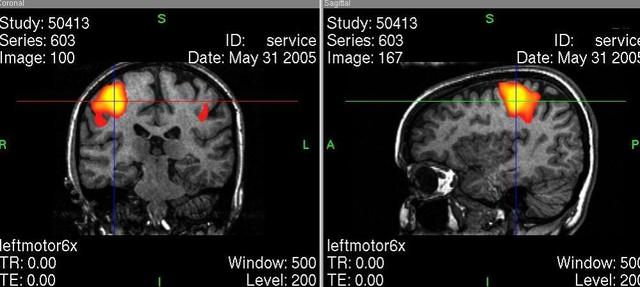

• Tomografia por Emision de Positrones (PET)

Tomografia por Emision de Positrones (PET)

-Inventor: Doctor Bownell.

-En 1927 se descubre teorica y experimentalmente el positron por P.A.M. Dirac.

-Es un estudio por imágenes donde se utiliza una sustancia radiactiva llamada marcador para buscar una patología en el cerebro.

-se crea una nueva version dell tomografo incrementando la sensibilidad y la posibilidad de obtener imagenes 3D.